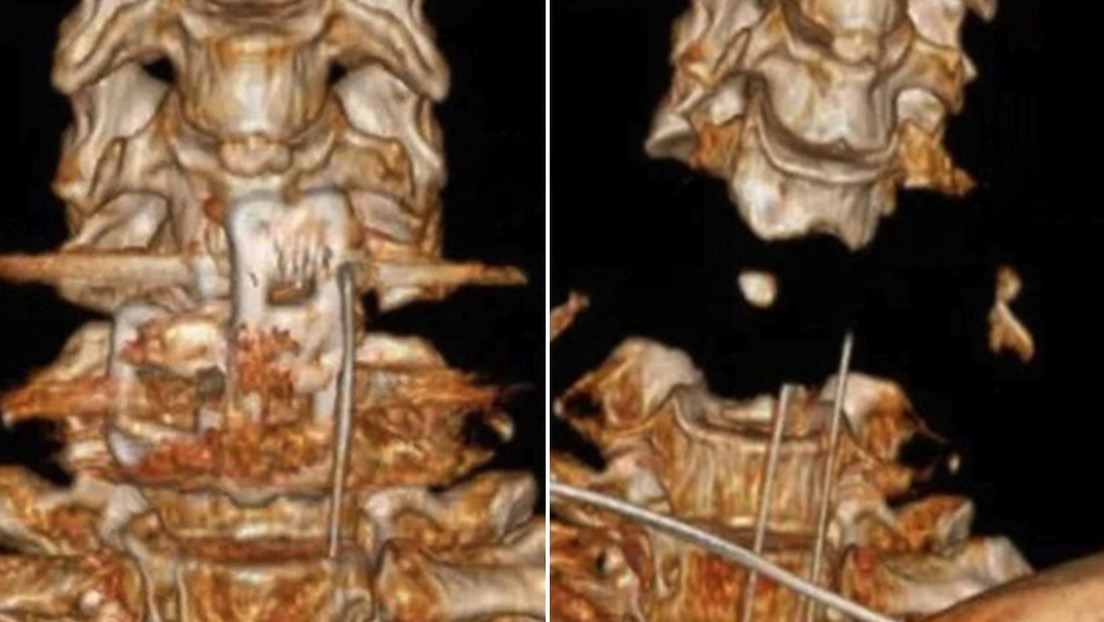

Un equipo médico en China realizó una cirugía milagrosa en la columna vertebral y el cráneo de un hombre, después de que un brazo robótico casi lo decapitara, informaron medios locales.

La información sobre el nuevo caso de salvación médica extraordinaria, indica que, el hombre resultó golpeado por el aparato, en un accidente que le provocó un desplazamiento de la columna vertebral y la cabeza, además de un ataque cardíaco y parálisis instantánea.

Precisó que revisaron mucha literatura en el país y en el extranjero, pero nunca se habían encontrado con un caso de separación de vértebras cervicales tan graves y mucho menos uno que sobreviviera luego del tratamiento.

A pesar de los riesgos implicados en una cirugía sin precedentes, el equipo médico preparó un plan integral de intervención médica contemplando la posibilidad de un sangrado masivo incontrolable, colapso circulatorio y perfusión cerebral. Pese a todas las dificultades, la operación se llevó a cabo con éxito en un lapso de tres horas.